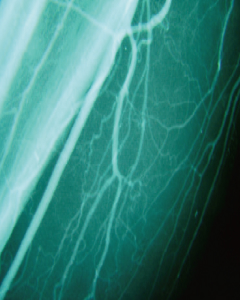

버거씨병

Buerger’s Disease-

- 하지 혈류 개선

- 치료 후 종아리 근육부위에 새로운 혈관이 형성되었고 혈류의 흐름이 호전되었습니다.

- 족부 혈류 개선

- 치료 후 종아리 족부에 새로운 혈관이 형성되었고 혈류의 흐름이 호전되었습니다.